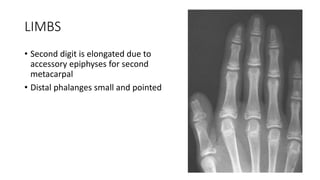

• Second digit is elongated due to

accessory epiphyses for second

metacarpal

• Distal phalanges small and pointed